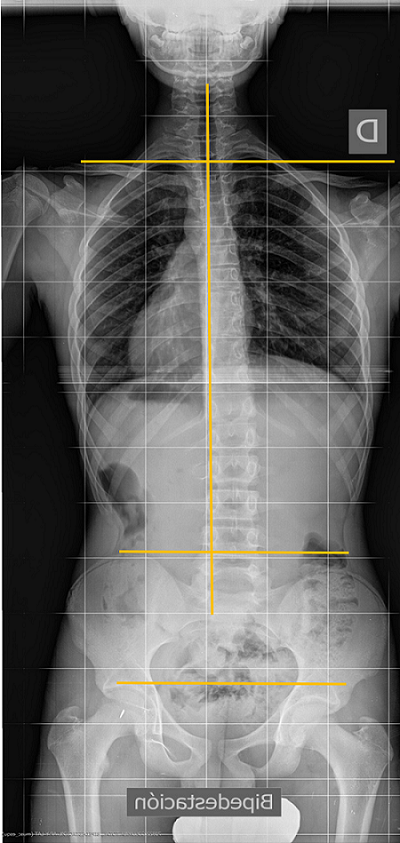

En cuanto a las imágenes de vértebras rotadas, si el paciente gira el tronco, o si la placa no incide perpendicular al plano coronal del paciente, aun manteniendo la pelvis centrada, pueden verse giradas, con un falso índice de Moe (se explica más adelante). Por eso es muy importante visualizar los puntos que permiten valorar la simetría de una proyección correcta (Figura 7).

Figura 7. La L2 está muy rotada, como correspondería a una curva más grave, pero comprobamos que radiografía no está perfectamente simétrica, porque en la zona isquiopubiana los agujeros obturadores no se ven simétricos. Todo el tronco está rotado. A veces es difícil analizar estos agujeros porque se tapan con el plomo protector de los ovarios, o porque se colima tanto que se cortan la pelvis y los agujeros. Mostrar/ocultar